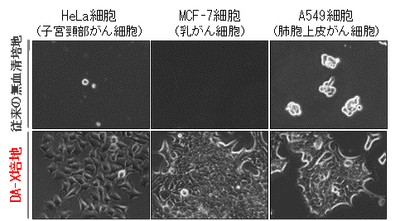

従来の無血清培地では、多くのがん細胞株が剥離して細胞死を起こします。それに対し、ダルベッコ変法イーグル培地※5、アルブミン※6、インスリン-トランスフェリン-セレニウム-エタノールアミン※7 を含み、培養皿にフィブロネクチン※8 をプレコートした無血清培地条件(DA-X培地コンディション)であれば、増殖性・接着性ともに良好であることが分かりました。それにより、これらの成分のすべてが、がん細胞株の生存・増殖に必須であると考えられました。また、肺がん・肝臓がん・子宮頸がん・乳がんなど様々な臓器・組織由来のがん細胞株でテストしたところ、DA-X培地はがん細胞種を選ばないユニバーサルな培地として利用可能であることがわかりました(下左図参照)。さらに、その分子メカニズムを解析したところ、DA-X培地コンディションが細胞膜のコレステロール量を最適化することで、良好な接着性・生存性をもたらしていることもわかりました(下右図参照)。